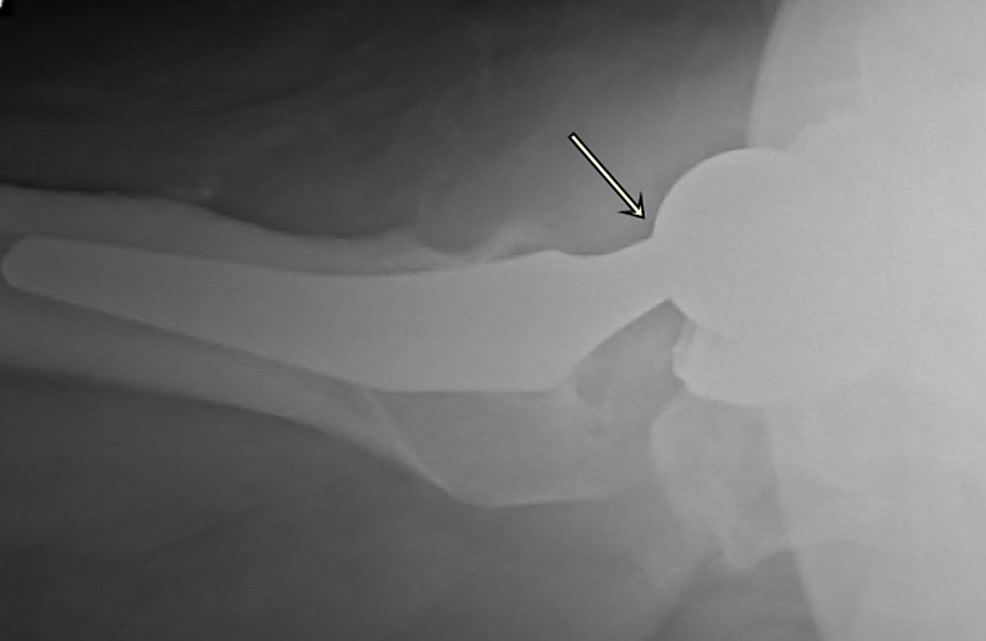

From www.researchgate.net

(PDF) Trunnionosis and prosthesis dissociation after total hip arthroplasty Trunnionosis Symptoms — tha trunnionosis is a complication of hip arthroplasty caused by metal ion release from corrosion at the femoral. — a wide range of signs and symptoms have been described for trunnionosis. — symptoms should first raise suspicion in order to diagnose a patient with trunnionosis. — symptoms of systemic toxicity include neurological (peripheral numbness, memory. Trunnionosis Symptoms.